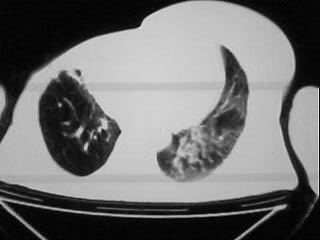

以下是引用随光逐影在2009-2-10 0:07:00的发言:[br]1)右肺放射性肺炎并节段性肺不张?请结合相关病史。2)右侧胸膜肥厚、粘连。3)心包膜增厚(或心包少量积液)。